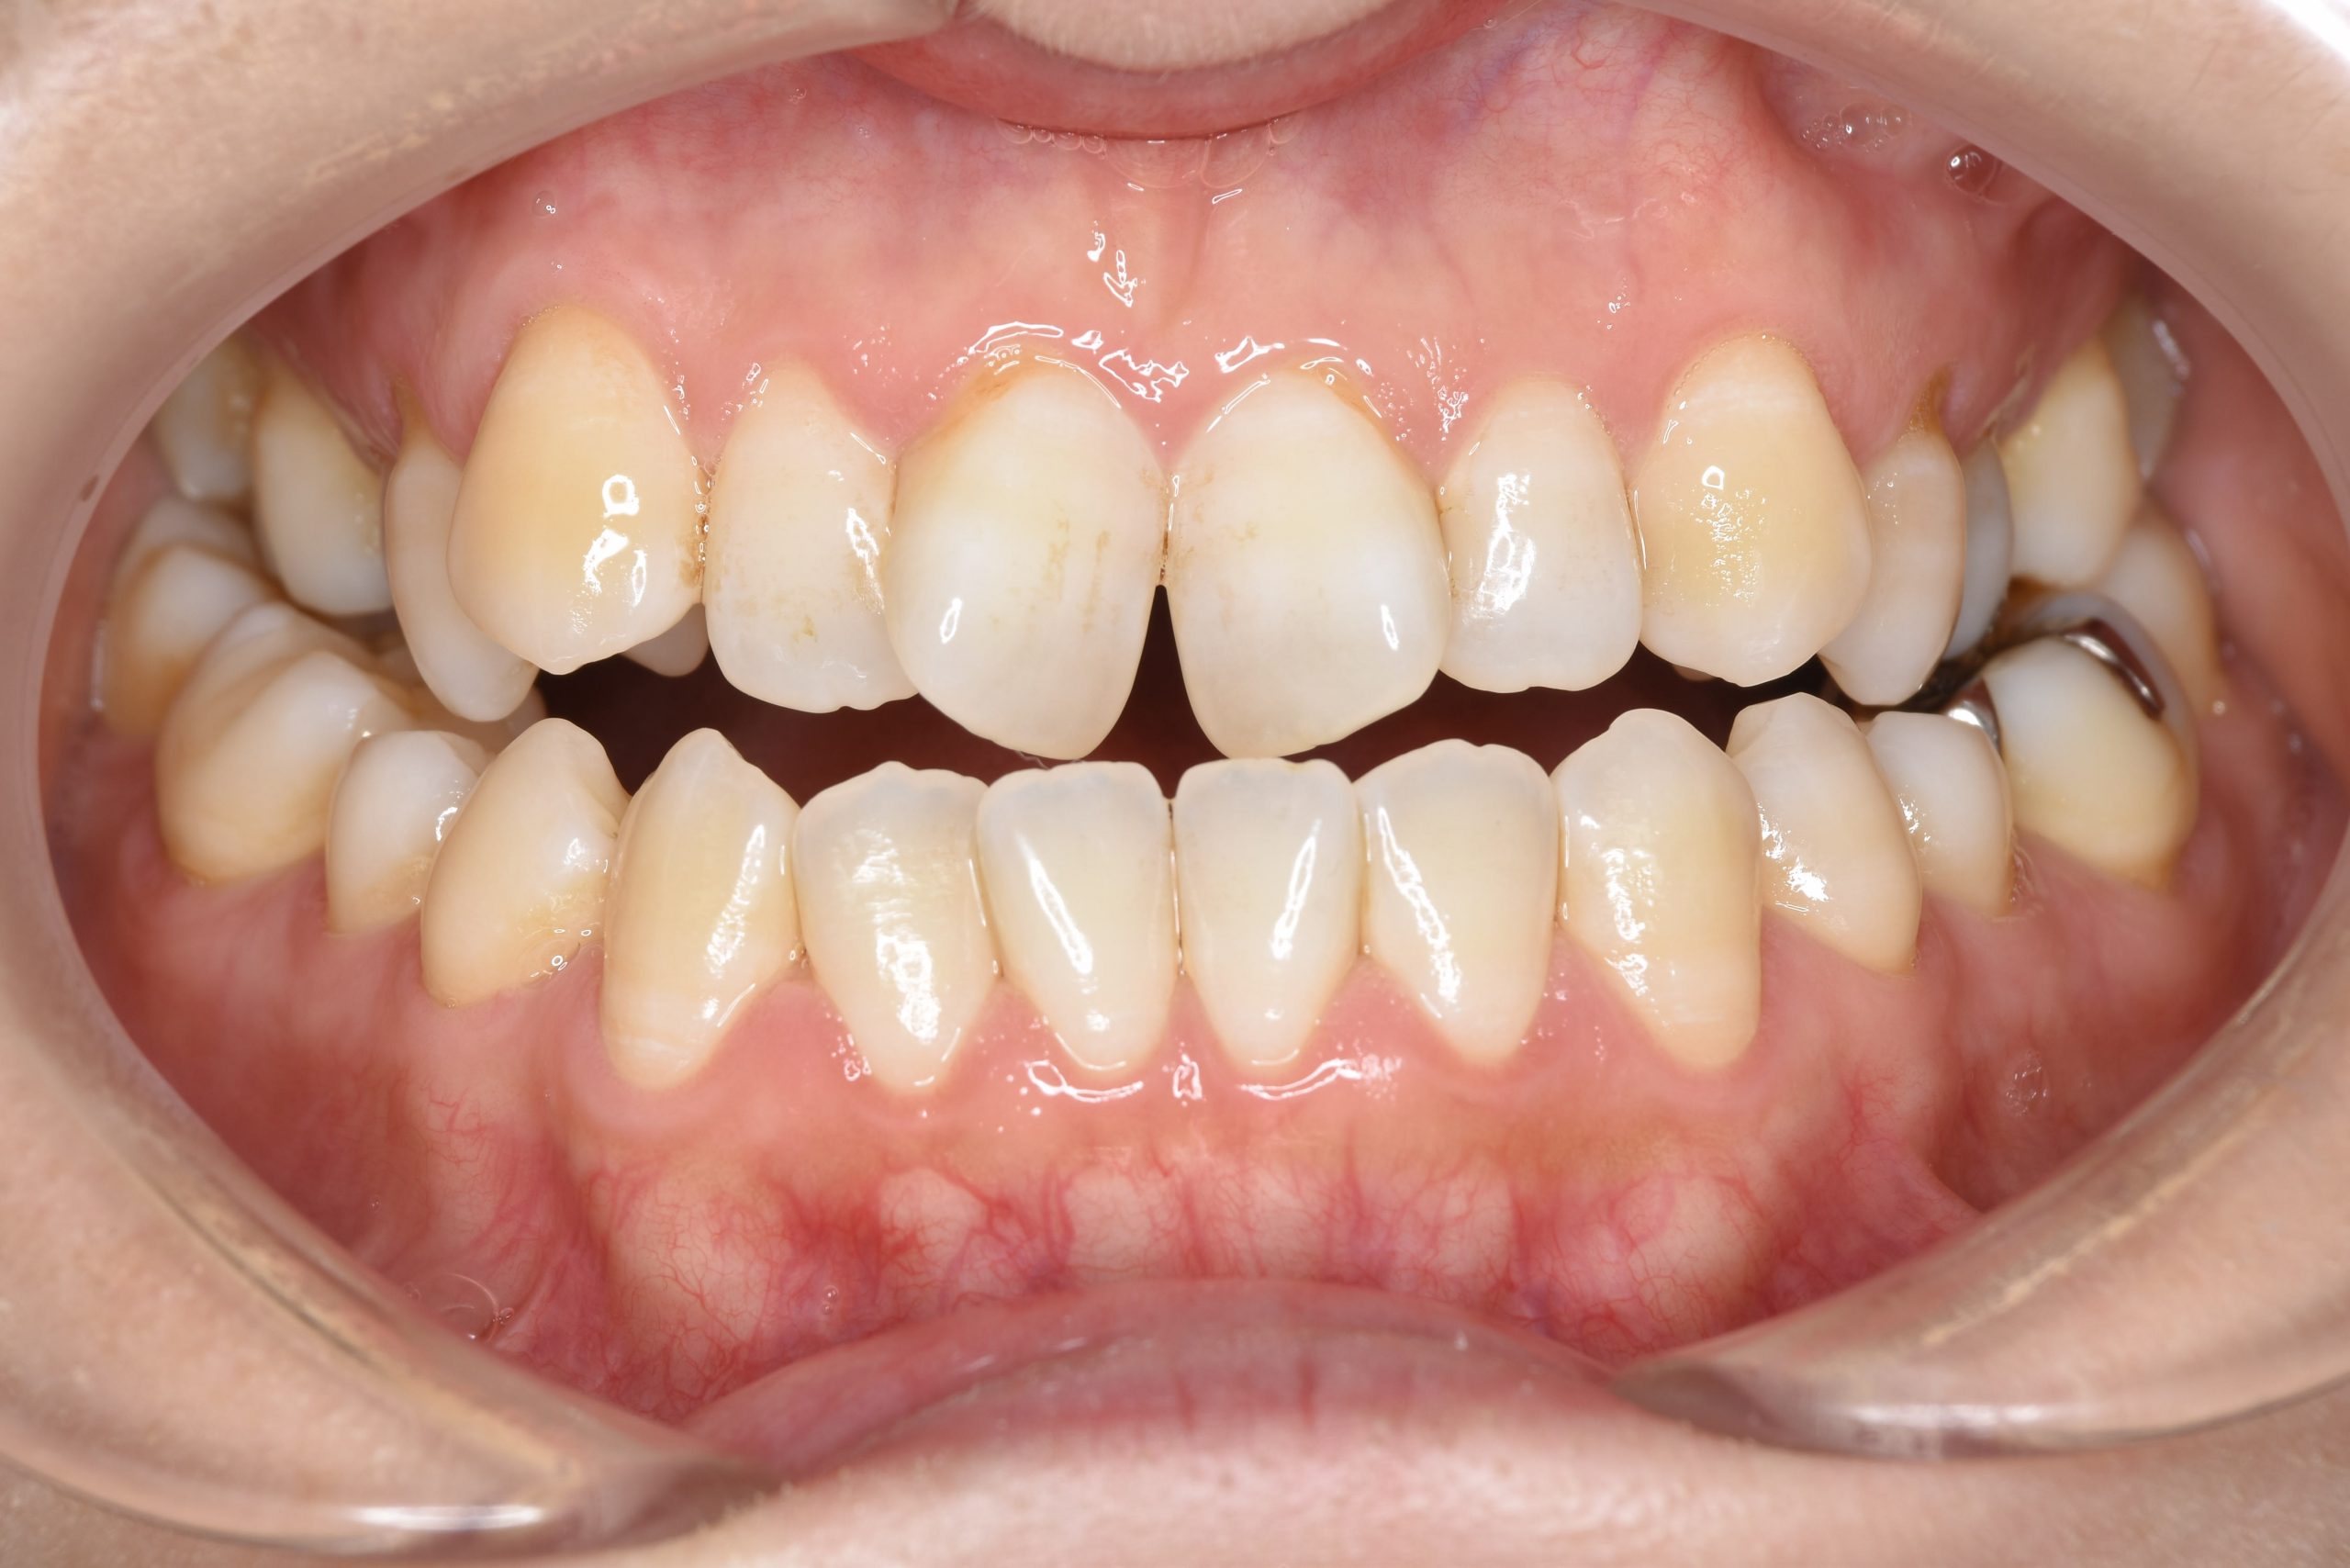

アフター

保険での矯正治療|症例_138

主訴 噛み合わせが悪い(反対)|歯並びが悪い|顎が出ている

施術内容 マルチブラケット装置を用いて歯牙を配列した後、

下顎骨離断術を行った。良好な咬合を獲得した。

治癒期間 3年8ヶ月間

費用 保険治療

リスク・副作用 違和感、不快感、痛み